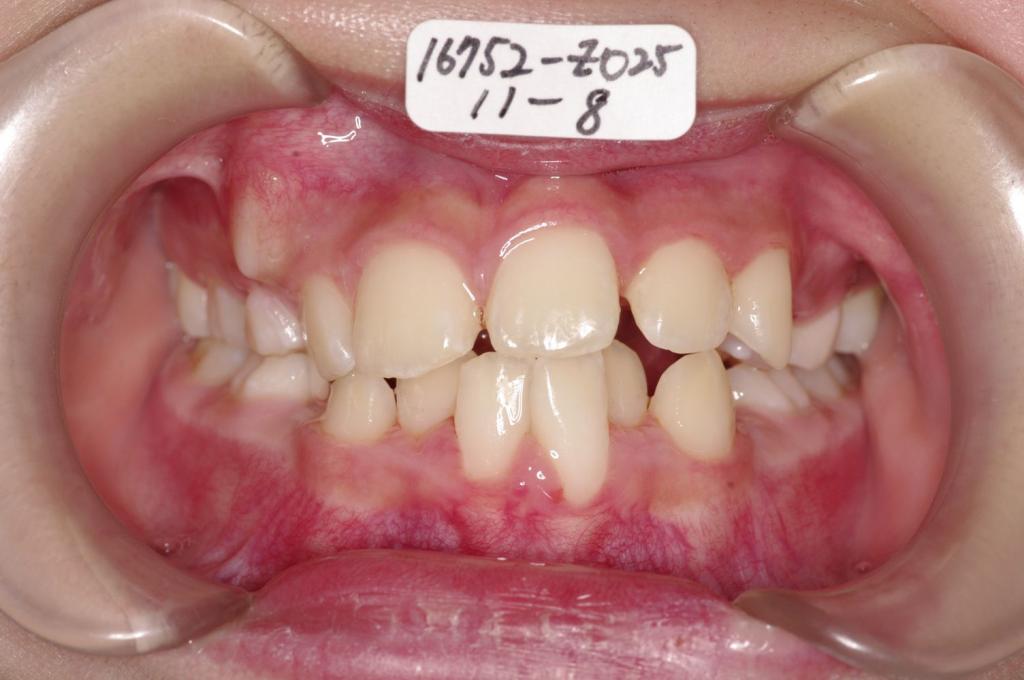

子供の矯正治療

(治療期間、治療前後写真、治療方法、費用)WORKS

下記の実績データをクリックして頂くと「性別」、「治療開始年齢」、「治療終了年齢」、「治療方法(矯正治療装置写真含む)」、「治療終了までの費用」など、詳細な矯正治療データをご覧頂けます。